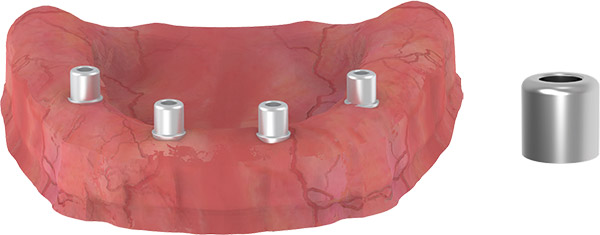

CLOSED TRAY IMPRESSION TECHNIQUE

- Use the straight and/or 17-degree Multi Base Ball Abutment in the anterior region.

- Use the 30-degree Multi Base Ball Abutment in the posterior region.

- Mount the plastic pick up transfers used for impression on 17-30 degree Multi Base Ball Abutments.

- Take the impression.

Note: The recommended insertion torque when screwing the abutment is 25 Ncm.